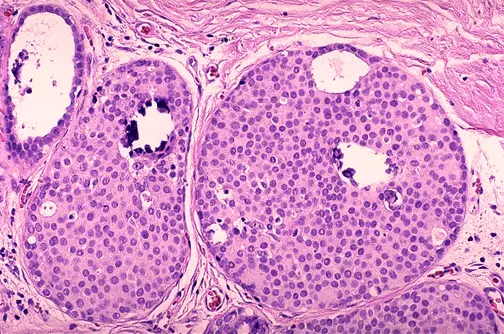

Carcinoma ductal de la mama uno de los muchos tipos de c�ncer de mama.